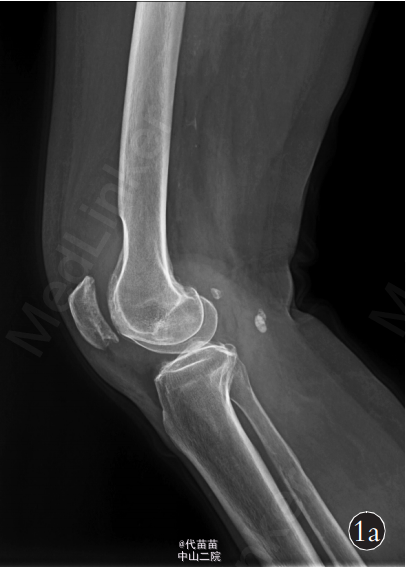

患者,女,70岁 。主因右膝关节间断性疼痛4年,加重2个月入院。患者自诉4年前无明显诱因出现膝关节间断性疼痛,活动时疼痛加重,休息后症状缓解,同时伴有右膝关节肿胀,膝关节活动时弹响症状明显,无夜间痛,未系统治疗。近2个月来患者疼痛症状逐渐加重,不能完全蹲下,并出现右小腿轻度肿胀。患者既往体健。查体:右膝关节肿胀,无发红及包块。右膝关节间隙按压痛阳性,浮髌试验阳性,髌骨摩擦试验阳性,右膝关节活动度:0°~130°,右下肢肌力Ⅳ级,其他检查未见异常。 影像学检查:X 线片示右侧膝关节不对称性变窄,关节面硬化,边缘可见唇样骨质增生,股骨下端凹槽样改变,边界较清楚,无骨膜反应,髌骨呈槽沟样改变(图 1a)。 右膝关节 CT 示右侧髌骨较薄,髌骨关节面锯齿样改变(图 1b)。MRI检查示膝关节腔内液体增多髌上囊内可见低信号影(图 1c)。为排除肿瘤及感染的可能性,进一步行实验室检查:血常规、ESR、CRP 及碱性磷酸酶以及 ECG 检查均未见异常。完善相关检查后, 择期行全膝关节表面置换术及滑膜清理术。为防止术后股骨缺损处出现病理性骨折,考虑选用制定型膝关节假体(股骨假体柄加长)。术中见:膝关节髌上囊内有大量陈旧性积血(图 1d),滑膜增生肥厚,股骨远端髁部上段可见轮廓清楚的凹陷性骨侵蚀面,股骨及胫骨骨赘形成,股骨髁及胫骨平台关节面软骨破坏,股骨外侧髁破坏严重,部分软骨下骨外露, 髌骨外侧变薄, 髌骨关节面有沟槽样凸凹不平(图1d),软骨面破坏,外侧较重,软骨下骨外露。 术中将病变关节囊及滑膜送检病理,快速病理回报:色素绒毛结节性滑膜炎可能性大。 术中彻底切除髌上囊、滑膜、髌下脂肪垫及半月板,切除胫骨表面、前十字韧带及后十字韧带,处理股骨髁,矫正 FTA 角为外翻 5°,安装 Depuy 公司 2 号股骨假体加长柄及2 号胫骨假体,胫骨假体上安装 8 mm 垫片,复位关节。检查内外侧软组织平衡良好,功能活动良好,此时行髌骨成形术,修理髌骨后见髌骨活动轨迹差, 缝合前向关节腔内软组织注入镇痛药物。 术后右侧膝关节侧位片示:假体固定位置良好,股骨加长柄通过股骨皮质缺损区(图 1e)。 术后病理诊断:色素绒毛结节性滑膜炎(图 1f)。 术后 24 h 拔除负压引流,伸直位